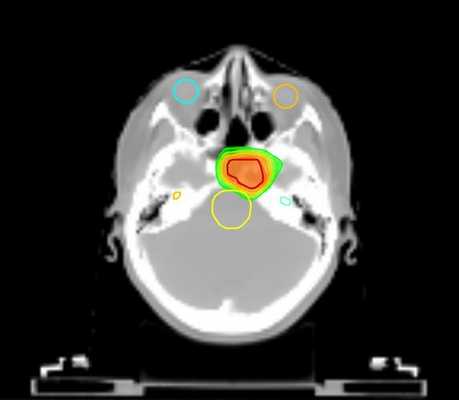

Tomotherapy в лечении доброкачественных опухолей головного мозга

Tomotherapy — это принципиально новая концепция лучевой терапии, которая сочетает элементы КТ-сканера с линейным ускорителем, чтобы точно скорректировать положение мишени и органов, находящихся в зоне риска, непосредственно перед лечением. Это особенно важно в отношении опухолей основания черепа, где они располагаются вблизи жизненно важных структур ствола мозга.

Tomotherapy уже активно применяется в ведущих онкоцентрах мира, где позволяет добиться хорошего результата лечения. Так, Джейкоб Ван Дейк из университета Онтарио сообщает об успешном облучении низко злокачественной глиомы и астроцитом, отмечая сохранение здоровой ткани. Аналогичные результаты получены и специалистами из других стран, что открывает принципиально новые возможности применив лучевой терапии.